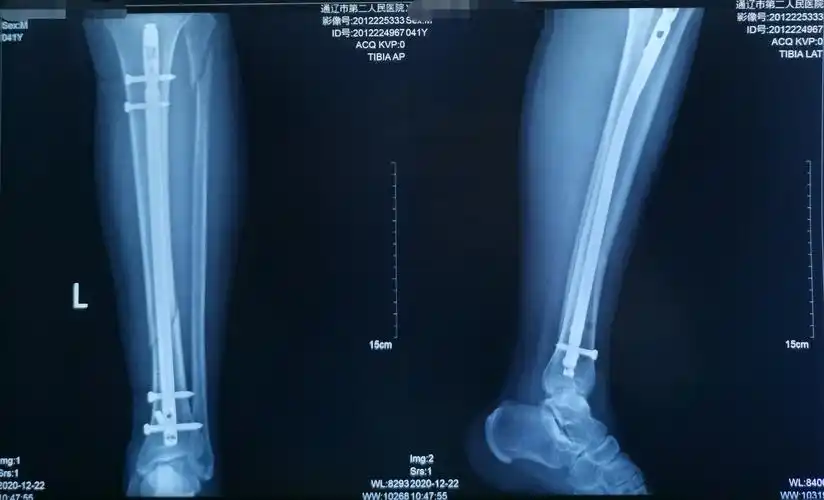

42岁胫腓骨骨折闭合复位髓内钉内固定手术一例